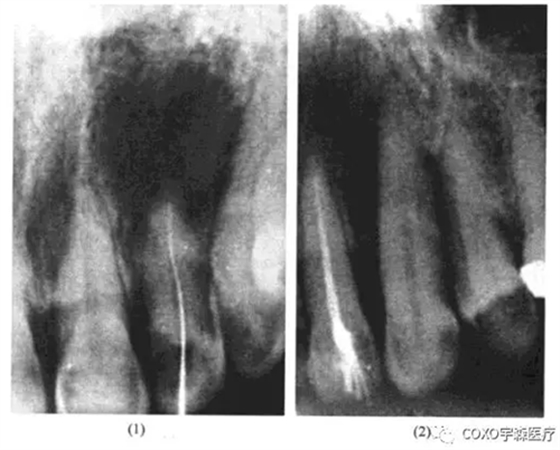

病例:

女性,54歲,左上唇炎癥腫脹一周在某中心醫(yī)院口腔科靜脈滴注抗生素未見(jiàn)好轉(zhuǎn)而來(lái)我科求治。檢查:[2唇側(cè)牙齦腫脹,有波動(dòng)感,[2無(wú)齲,無(wú)牙體缺損,牙髓活力測(cè)試反應(yīng)明顯,X線片示:[2根尖區(qū)有1cm×1.5cm之透射陰影,邊緣整齊。當(dāng)日處理:[2唇側(cè)切開(kāi)引流待急性炎癥消退后,在局麻下行活髓摘除術(shù),牙髓完整,3日后完成根管充填,并行囊腫摘除術(shù)。術(shù)中見(jiàn)[2唇側(cè)骨板有極小的穿破,按常規(guī)刮除炎性肉芽組織,肉芽多在[2之腭側(cè),送病理切片;手術(shù)診斷為2根尖周囊腫,病理診斷亦為[2根尖周囊腫;3個(gè)月后復(fù)查,2無(wú)癥狀,X線片示:原根尖周病變已痊愈(圖13-4)

分析與評(píng)述

由于[2為活髓牙,根尖周囊腫的診斷不能成立。由于X線片示囊腫位于[2之根尖而非[23之間,術(shù)中亦證實(shí)囊腫在[2之根尖偏腭側(cè),故球上頜囊腫之診斷亦可排除,最后診斷應(yīng)為切牙管囊腫。